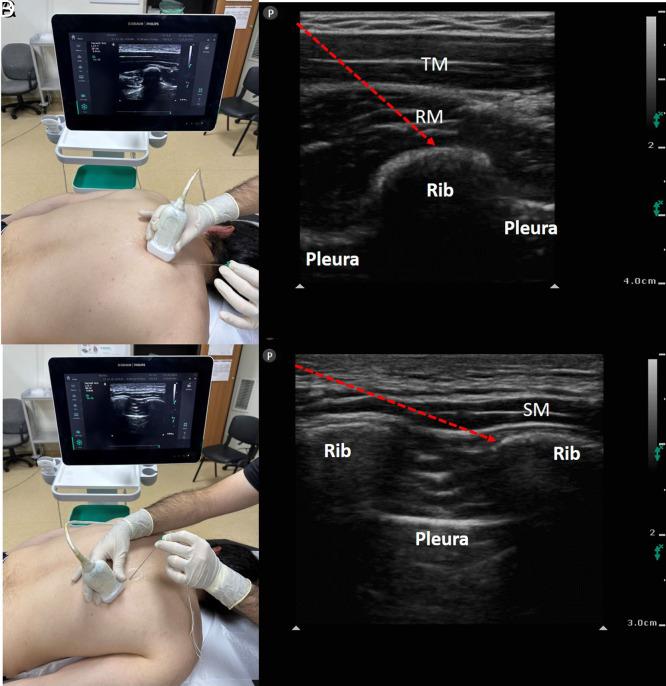

Regional anesthesia has benefits beyond just treating acute postoperative pain. Interfascial plane blocks, which have been very popular with ultrasound in recent years, function primarily by administering a high volume of a local anesthetic to the fascial plane. Contrary to traditional peripheral nerve blocks, the targeted nerve or structure in interfacial plane blocks is not fully defined, and the indications have not been fully revealed yet. Anatomical, cadaveric, and radiological studies show how effective the interfascial plane blocks play a role. This review focuses on the benefits, techniques, indications, and complications of interfascial plane blocks in the context of breast, thoracic, and orthopedic surgery.

区域麻醉的益处不仅仅局限于治疗术后急性疼痛。近年来,筋膜平面阻滞在超声引导下非常流行,其主要作用机制是在筋膜平面注射大量局部麻醉药。与传统的外周神经阻滞不同,筋膜平面阻滞中所针对的神经或结构尚未完全明确,其适应证也尚未完全揭示。解剖学、尸体研究和影像学研究表明了筋膜平面阻滞发挥作用的有效性。本综述重点关注在乳腺、胸科和骨科手术背景下筋膜平面阻滞的益处、技术、适应证及并发症。